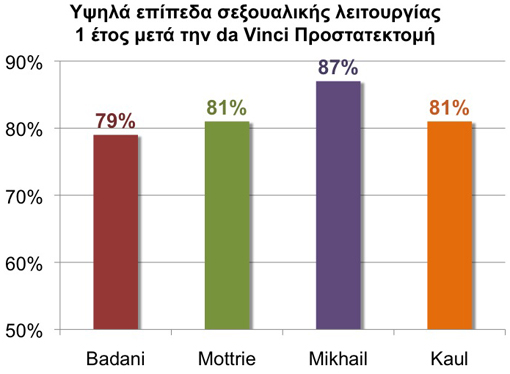

Οι ασθενείς με καρκίνο του προστάτη ανησυχούν επίσης για την εγκράτεια των ούρων και την σεξουαλική λειτουργία μετά την θεραπεία. Όλες οι μέχρι τώρα μεγάλες μελέτες δείχνουν ότι η da Vinci προστατεκτομή παρουσιάζει γρηγορότερη επάνοδο της εγκράτειας των ούρων και χαμηλότερα ποσοστά πόνου σε σύγκριση με τους ασθενείς που υποβλήθηκαν σε ακτινοθεραπεία (βραχυθεραπεία). Διάφορες επίσης μελέτες δείχνουν ότι οι ασθενείς που ήταν προηγουμένως σεξουαλικά ικανοί παρουσιάζουν πλήρη ανάρρωση της σεξουαλικής τους λειτουργίας (οριζόμενη σαν στύση ικανή για κολπική διείσδυση) μέσα σ’ ένα έτος από την da Vinci προστατεκτομη. Η περίοδος ανάρρωσης μπορεί να επιταχυνθεί μέσω ενός ειδικού προγράμματος ανάρρωσης της στυτικής λειτουργίας με την χρήση ασκήσεων και φαρμάκων.

Σεξουαλική λειτουργία

Ο προστάτης περιβάλλεται από λεπτά στρώματα νεύρων που υποστηρίζουν την στυτική λειτουργία. Πολλοί ασθενείς είναι υποψήφιοι για μία νευροπροστατευτική προστατεκτομή, αφαιρώντας ριζικά τον καρκινωματώδη προστάτη αλλά διατηρώντας στον μέγιστο βαθμό τα στυτικά νεύρα.

Ποσοστά επανόδου της στύσης 1 έτος μετά την da Vinci Προστατεκτομή. Τα ονόματα παραπέμπουν στους συγγραφείς των μελετών.

Διάφορες μελέτες έδειξαν ότι ασθενείς που ήταν προεγχειρητικά σεξουαλικά ικανοί παρουσιάζουν υψηλότερα επίπεδα ανάρρωσης της σεξουαλικής λειτουργίας (οριζόμενη σαν στύση ικανή για κολπική διείσδυση) μέσα σ’ ένα χρόνο μετά την da Vinci Ριζική Προστατεκτομή. Εφαρμόζοντας ένα μετεγχειρητικό πρόγραμμα ανάρρωσης της σεξουαλικής λειτουργίας με φάρμακα και ειδικές ασκήσεις μπορεί να επιταχυνθεί η επάνοδος της αυτόματης στύσης.